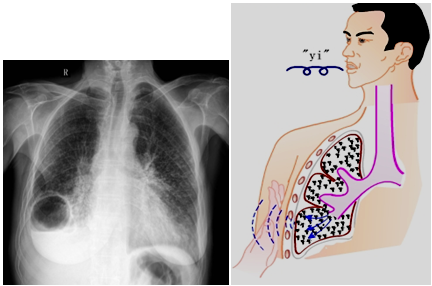

临床助理医师(2021)-核心考点